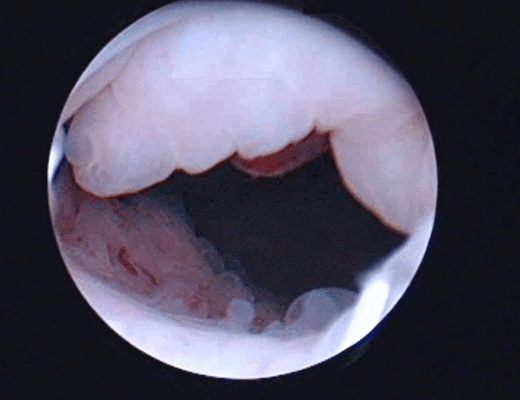

Цистоскопическое обследование пациента С.

Цистоскопическая картина солидного образования, вдающегося в полость мочевого пузыря в виде массивных бугристых масс, покрытых отечной слизистой оболочкой

У 1 пациентки К., 36 лет, по данным эндоскопического исследования выявлено папиллярное образование на тонком основании размером 1 см в диаметре.

Цистоскопическое обследование пациентки К.

Цистоскопическая картина солидного образования, вдающегося в полость мочевого пузыря